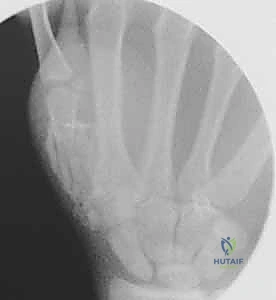

- الأشعة السينية (X-rays): يتم أخذ صور من زوايا متعددة (أمامية خلفية، جانبية، ومائلة) لتحديد موقع الكسر، نوعه (عرضي، حلزوني، مائل، متفتت)، ودرجة التزوي (Angulation).

خطوات التثبيت الجراحي - توثيق بصري (Intraoperative Imaging)

يحرص الدكتور هطيف على توثيق خطوات العمل الجراحي لضمان أعلى مستويات الدقة. نستعرض هنا مجموعة من الصور من داخل غرفة العمليات توضح مدى تعقيد ودقة هذه الجراحات:

معرض الصور الشعاعية: تقييم النتائج الجراحية (Post-Op X-rays)

النجاح الحقيقي يُقاس بالاستعادة المثالية للشكل التشريحي للعظم. توضح هذه الصور الشعاعية بعد الجراحة الدقة المتناهية في إعادة محاذاة العظام وتثبيتها.

التثبيت المحكم يسمح بالشفاء العظمي الأولي (Primary Bone Healing) دون تكوين كتلة عظمية كبيرة (Callus) قد تعيق حركة الأوتار المنزلقة فوقها.